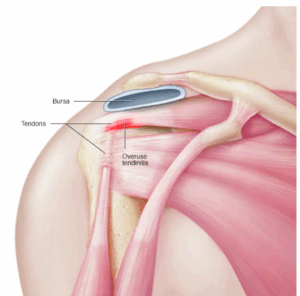

Tendinitis (all)

Tendinitis is inflammation of the thick fibrous cords that attach muscle to bone. These cords are called tendons. The condition causes pain and tenderness just outside a joint.

Tendinopathy

Tendinopathy is a term for any condition that affects a tendon. Tendons are cords that attach muscle to bone. Tendinopathy, which can cause pain and tenderness, is common. It is often caused by overuse or repeated movement and tends to affect certain tendons in the arm or leg.